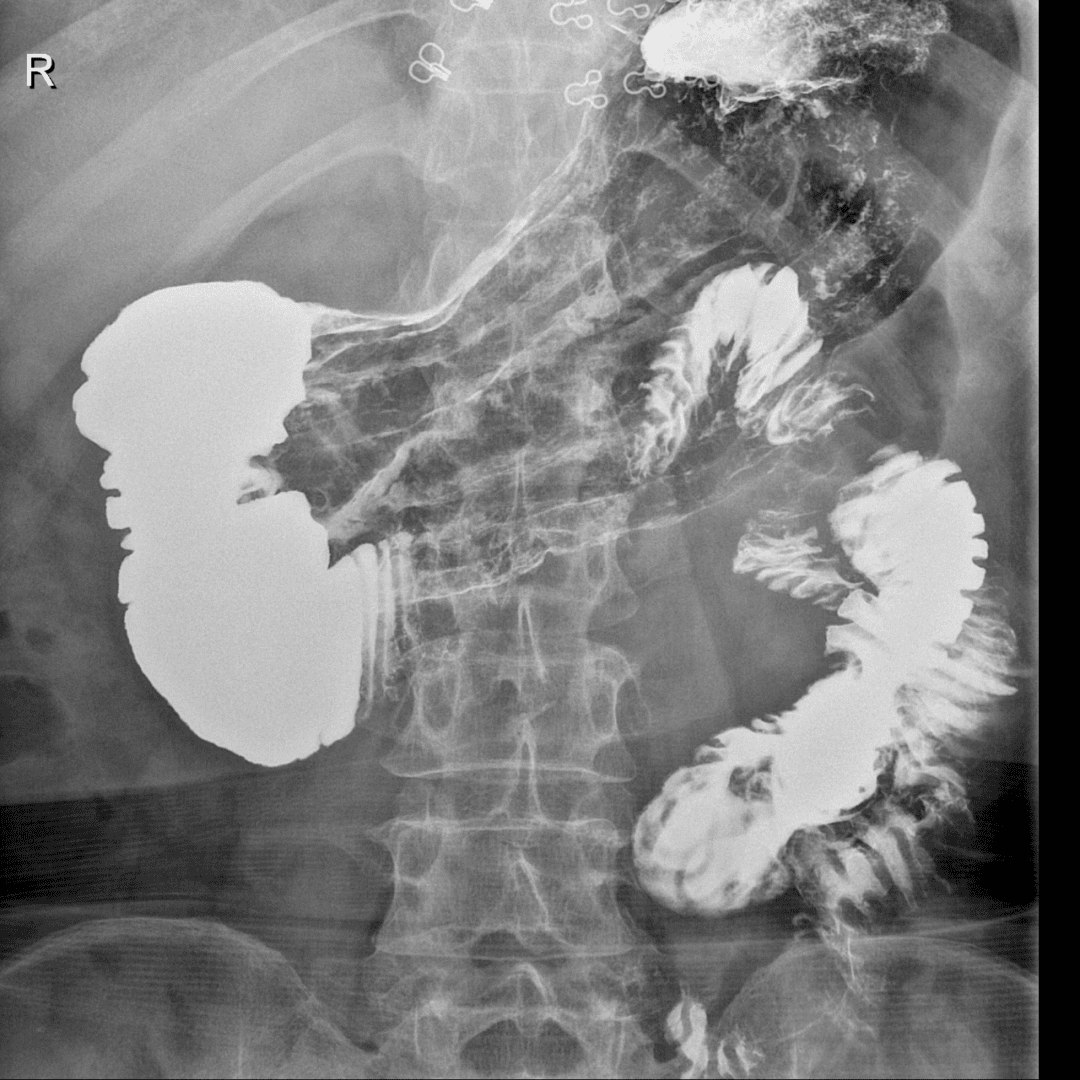

辅助检查:血、大小便及心电常规正常。免疫过筛、肝功能等正常。上腹部CT平扫未见异常。纤维胃镜示表浅性糜烂。上消化道气钡双重造影示:食管、胃腔、十二指肠上段、降段显影正常。十二指肠水平部造影剂停滞不前,呈“笔杆”状截断,改变体位后,胃腔蠕动数次后造影剂迅速通过水平部截断处。

诊断:肠系膜上动脉压迫综合症。外科给予十二指肠空肠吻合术。

上消化道气钡双重造影为主要诊断方法。初次超声及CT检查无器质性病变容易漏诊,针对性测量肠系膜上动脉与腹主动脉夹角(<20°,正常为40°~60°)可明确诊断。